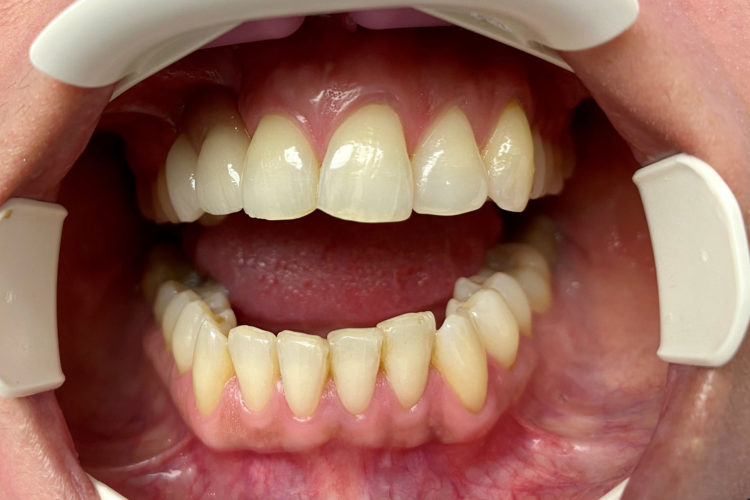

Pacienta in varsta de 39 de ani, a venit in clinica cu pierdere osoasa majora la maxilar in urma unei extractii de canin inclus si pierderea dintelui invecinat. Dupa o interventie de aditie osoasa, pacienta a primit  2 implante DENTIUM pe care s-a efectuat o protezare fizionomica fixa (baza titan plus suprastructura insurubata de zirconiu), cu refacerea conturului gingival si restaurarea functionala a arcadei. Pacientei i s-a propus si redresarea ortodontica pe care a amanat-o pentru o data ulterioara.